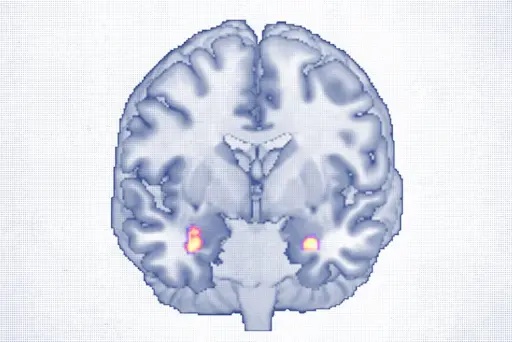

フロスを面倒に感じる人もいるかもしれません。しかし、新しい研究により、フロスは努力する価値があるという証拠がまたひとつ加わりました。血栓や不整脈に起因する脳卒中のリスクを軽減する可能性があるからです。予備研究では、口内に存在する一般的な細菌が脳卒中のリスクを高める可能性があることが判明し、研究を裏付ける結果となりました。

研究者らは、フロッシングと虚血性脳卒中(脳動脈の血栓)のリスク22%低下、心臓から移動した血栓による脳卒中のリスク44%低下との関連性を指摘しました。また、フロッシングは心房細動のリスク12%低下とも関連しており、虫歯や歯周病の可能性も低減させることが分かりました。しかし、フロッシングの頻度と血栓性脳卒中や「ラクナ梗塞による脳卒中」のリスク低下との間に関連性は認められませんでした。

著者らは、口腔内や腸内に広く存在する「Streptococcus anginosus(ストレプトコッカス・アンギノサス)」という細菌が、脳卒中を患ったことのある人の腸内に大量に存在していることを発見しました。また、この細菌はより深刻な予後と高い死亡率にも関連しています。

研究者らは、心血管疾患と脳卒中との関連性の根底にある可能性について仮説を立てています。 歯周病の歯垢に含まれる細菌が血流に入り込み、血小板を活性化させます。血小板が活性化すると凝集して血栓を形成し、心血管系の疾患を引き起こす可能性があります。

また、血小板の活性化は炎症性物質の分泌を促し、動脈の脂肪性プラーク(粥状硬化)の形成や血栓(血栓症)の原因となることもあります。これらの炎症性物質は全身性炎症を引き起こす可能性があり、これも一因であると考えられています。